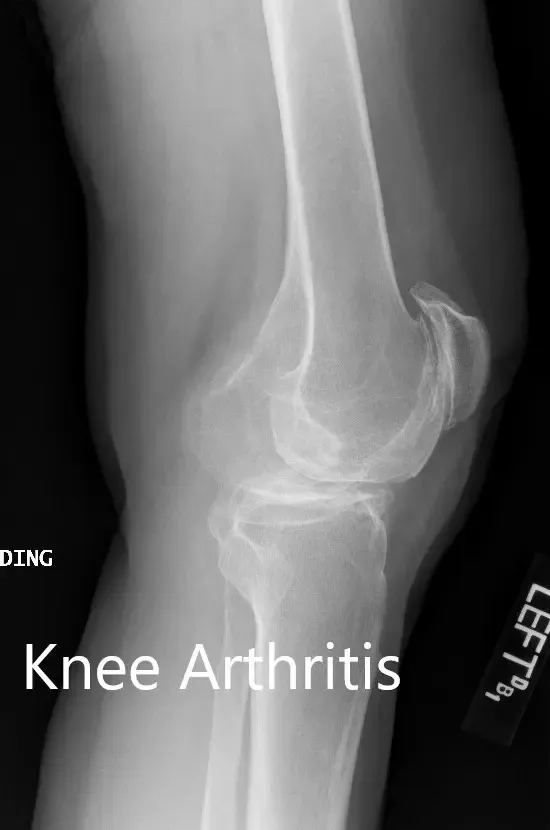

Los estudios de imagen realizados revelaron osteoartritis tricompartmental severa en ambas rodillas. Teniendo en cuenta que su estilo de vida limitaba el dolor de rodilla y el agotamiento de opciones conservadoras de manejo, le recomendaron un reemplazo bilateral de rodilla. Se le consideró candidato para un reemplazo total de rodilla personalizado. Él estuvo de acuerdo con el plan.

Radiografía preoperatoria que muestra las vistas laterales de la rodilla derecha e izquierda respectivamente